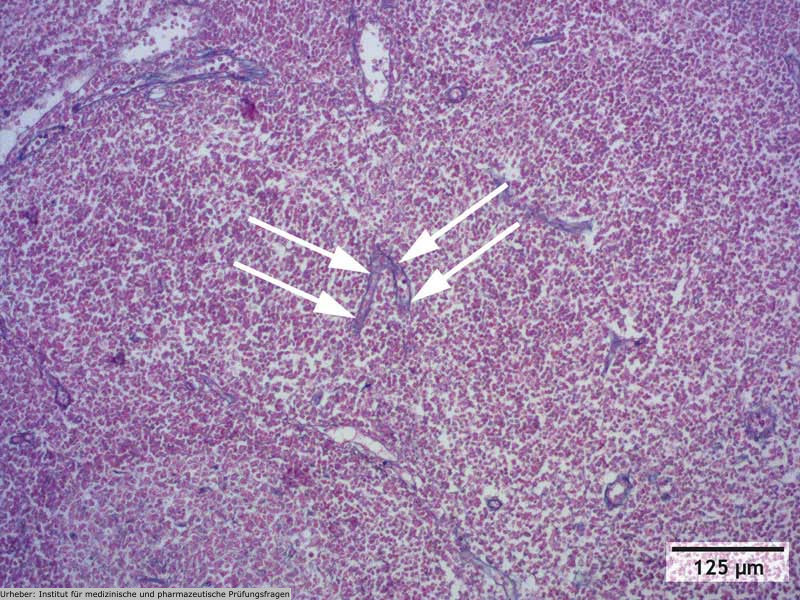

2.29 Die dargestellten Abbildungen zeigen ein lymphatisches Organ in verschiedenen Vergrößerungsstufen, wobei eine特定的 Struktur jeweils mit Pfeilen gekennzeichnet ist. In welchem der folgenden lymphatischen Organe ist das Auftreten dieser markierten Struktur am unwahrscheinlichsten?

- (A) im Darm-assoziierten lymphatischen Gewebe (GALT)

- (B) in der Tonsilla palatina

- (C) in den Lymphknoten

- (D) in der Tonsilla pharyngea

- (E) in der Milz